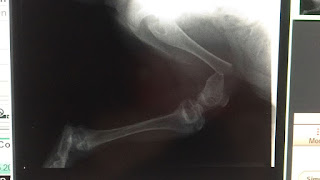

Tras la retirada de las banderillas y divisa realizamos la cura del animal. Un puyazo en lo alto de 25 cm con trayectoria descendente .